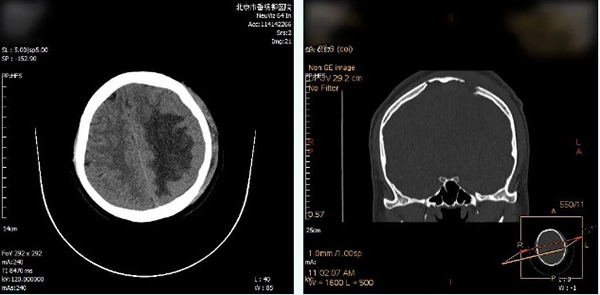

▲手术后的CT检查显示

刺入脑组织中的骨折碎片已全部取出

没有继发颅内出血